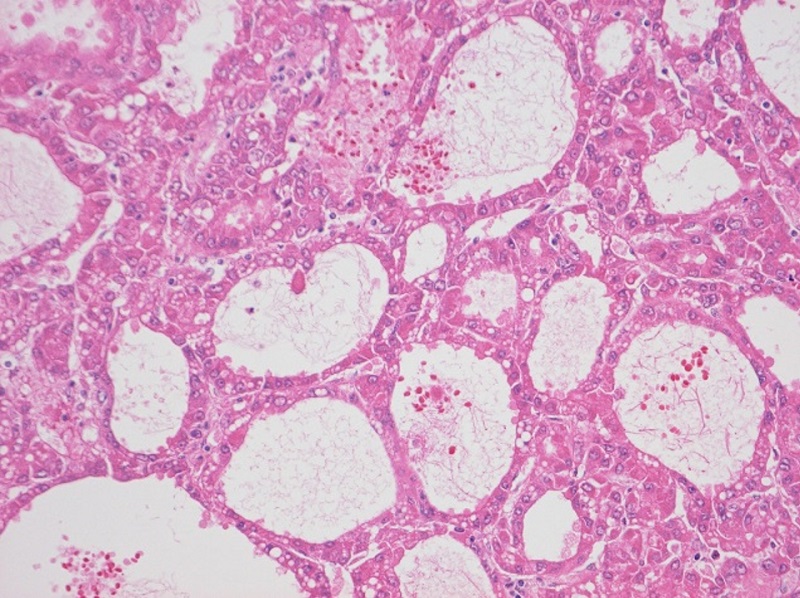

図4 腫瘍の拡大図

いわゆる偽腺管パターン(pseudoglandular pattern)を示す.

若 杉:これは……,いわゆる偽腺管パターンですね.

市 原:そうです.偽腺管パターン(pseudoglandular pattern)は,HCCにみられる細胞配列のバリエーションです.特殊な所見というわけではなく,HCCを顕微鏡で見ると,どこか一部にみられることが比較的多いです.ただ本例においては,病変のかなり多くの領域が偽腺腔を形成しています.これほど多いのは少し珍しいですかね.

若 杉:そうか,脂肪ではなく,腺腔の繰り返しのせいで高エコーになっているというわけですか.

長谷川:なるほど,本編でもふれたように,音響インピーダンスの差ができますからね.

市 原:それで私が顕微鏡を見てみたら,高エコーの主原因は脂肪沈着ではなくpseudoglandular patternだったことがわかったんです.このパターンは,高分化型から中分化型になりかけているようなHCCに比較的多くみられます.